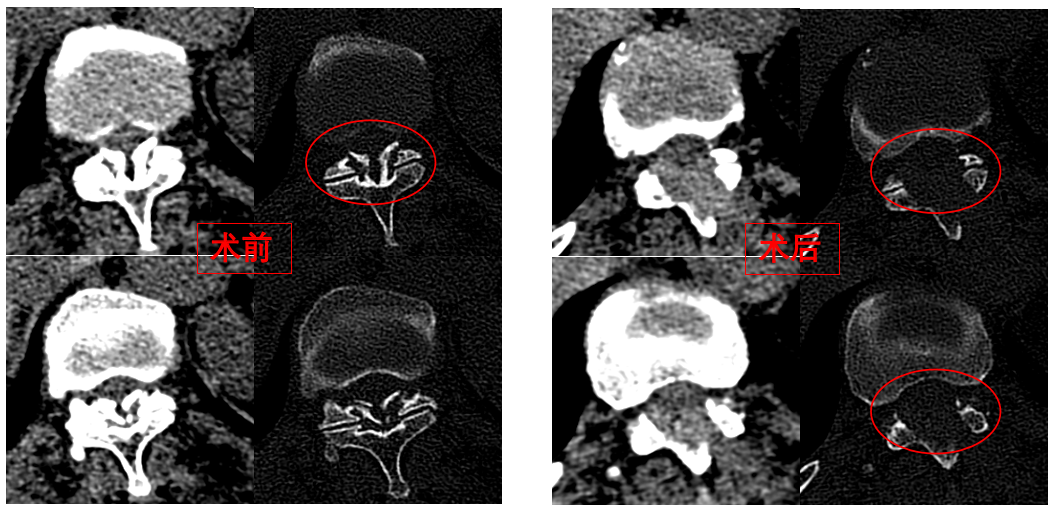

華西醫(yī)院成辦分院骨科副主任醫(yī)師張斌接診后,憑借豐富的脊柱治療經(jīng)驗(yàn),立即安排卓瑪阿媽做了系列精密檢查,檢查結(jié)果顯示,阿媽胸椎11/12節(jié)段黃韌帶嚴(yán)重骨化,導(dǎo)致椎管顯著狹窄,脊髓受壓,確診為嚴(yán)重的“胸椎黃韌帶骨化癥”,如果不及時手術(shù)最終可能面臨癱瘓的風(fēng)險。

手術(shù)歷時一個半小時,骨科脊柱微創(chuàng)團(tuán)隊(duì)成功完整切除了壓迫脊髓的骨化黃韌帶,徹底解除了卓瑪阿媽的脊髓壓迫。手術(shù)過程順利,手術(shù)切口僅1厘米。

圖為卓瑪阿媽術(shù)前、術(shù)后胸椎CT照片對比。